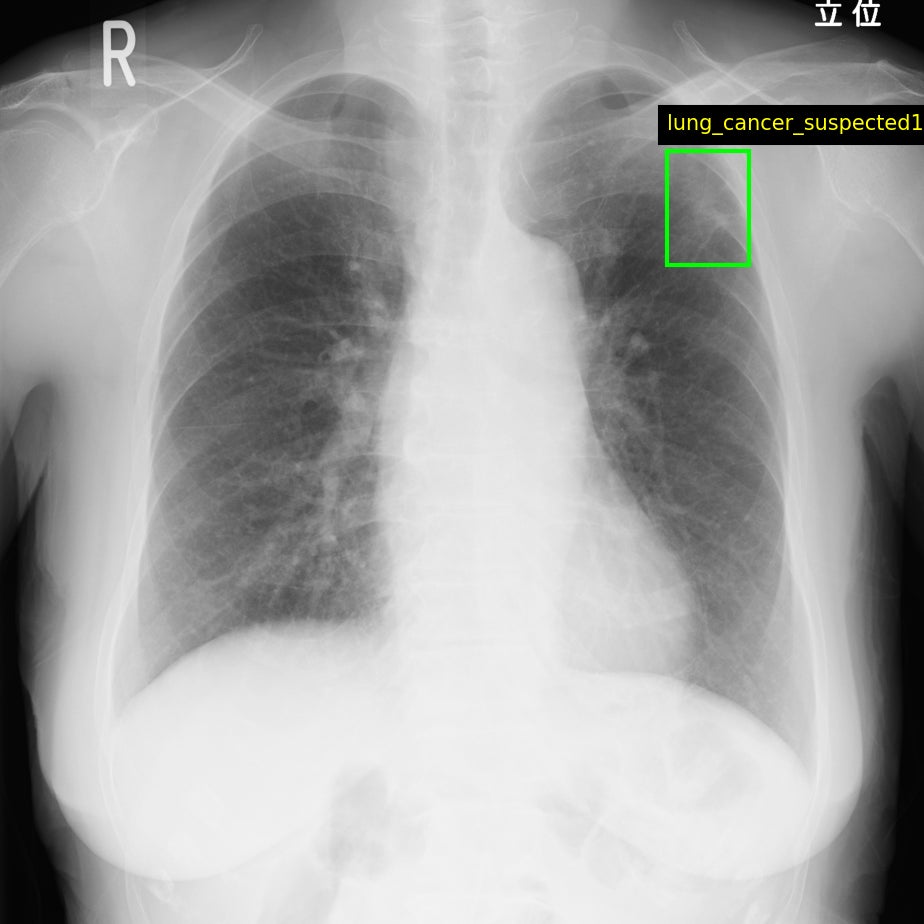

Callisto DataHub 2周年を記念し、専門医が作成した病変BBox付きの肺がん疑いX線データセット 50症例と、病変セグメンテーション付きの前立腺がんMRIデータセット(PI-RADS 4・5) 50症例を無料配布しています。前立腺がんMRIデータセットには、T1w, T2w, DWI, ADC, (あれば)DCEが含まれます。いずれも日本の医療施設由来で、所見文付き・商用利用可能なデータセットです。